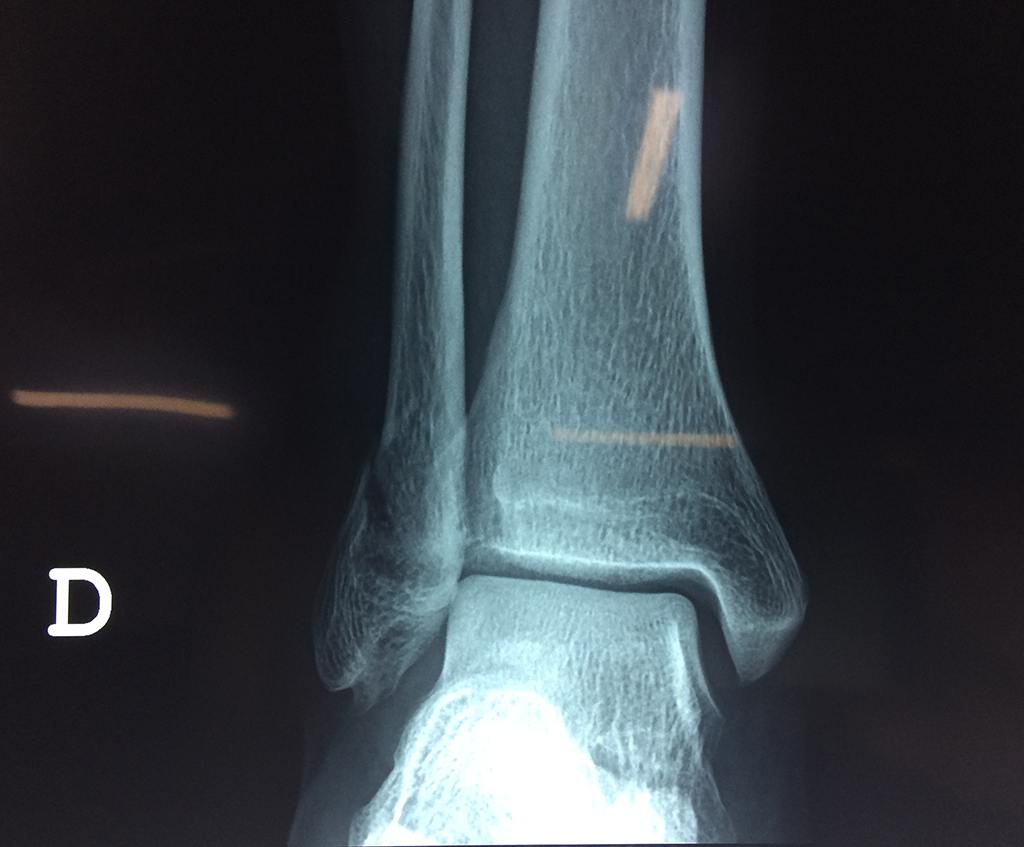

Una fractura de tobillo es la rotura de uno o más de los huesos del tobillo. Estas fracturas pueden ser:

Algunas fracturas de tobillo pueden requerir cirugía si:

- Los extremos de los huesos están desalineados entre sí (desplazados).

- La fractura se extiende hasta la articulación del tobillo (fractura intra-articular).

- Los tendones o ligamentos (tejidos que sujetan los músculos y los huesos entre sí) están rotos.

Cuando se necesita cirugía, es probable que esta implique el uso de clavijas de metal, tornillos o placas para sostener los huesos en su lugar mientras la fractura se consolida. Los elementos de soporte pueden ser temporales o permanentes.